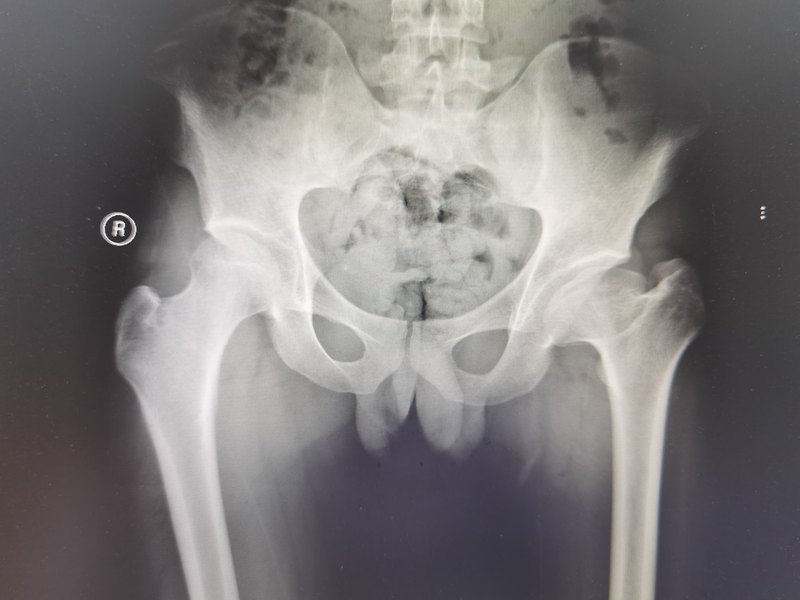

1)發(fā)生原因不太明確,有時(shí)可能和孩子長(zhǎng)期、高強(qiáng)度運(yùn)動(dòng)相關(guān)的反復(fù)輕微外傷有關(guān)。發(fā)生機(jī)制可能和局部微循環(huán)障礙、股骨頭血供不足有關(guān);2)大齡兒童股骨頭缺血壞死進(jìn)展非常迅速,和Perthes相比,自然病程進(jìn)展變化更迅速,更需要及時(shí)、有效干預(yù),避免錯(cuò)失寶貴時(shí)機(jī);3)導(dǎo)致股骨頭缺血壞死屬于“內(nèi)因”,目前并沒(méi)有特別好的“控制”措施;4)股骨頭缺血壞死后會(huì)逐漸修復(fù),但是,在這個(gè)過(guò)程中,股骨頭可能會(huì)逐漸變形,并且定型,股骨頭變形、髖臼-股骨頭不匹配會(huì)大大增加髖關(guān)節(jié)退行性變的風(fēng)險(xiǎn);5)在碎裂期,經(jīng)常在髖臼外緣處出現(xiàn)“縱向裂隙”/節(jié)裂,提示病程發(fā)展變化和股骨頭包容不良、應(yīng)力集中、力學(xué)環(huán)境有關(guān);6)股骨頭包容不良屬于“外患”,是外科醫(yī)生需要干預(yù)也是能夠干預(yù)的;7)就干預(yù)時(shí)機(jī)來(lái)說(shuō),需要及時(shí)/盡快干預(yù),改善包容;8)干預(yù)的手段比較多,例如外展支具保守治療、跨髖關(guān)節(jié)外固定架、骨盆/股骨近端截骨術(shù),跨髖關(guān)節(jié)外固定架是沒(méi)有辦法的辦法,可以實(shí)現(xiàn)“關(guān)節(jié)牽開(kāi)”的效果,類似于長(zhǎng)期“免負(fù)重”,不過(guò)對(duì)改善髖關(guān)節(jié)包容作用相對(duì)有限。并且,這種外架護(hù)理起來(lái)非常困難,孩子、家長(zhǎng)以及主治醫(yī)生都會(huì)非常困難/痛苦;9)對(duì)已呈現(xiàn)包容不良的情況,首選“骨盆Chiari骨盆內(nèi)移截骨術(shù)”,護(hù)理簡(jiǎn)單,恢復(fù)快速,多數(shù)恢復(fù)還不錯(cuò)。根據(jù)TJPO經(jīng)驗(yàn),對(duì)于大齡兒童股骨頭缺血壞死,是性價(jià)比最高的治療選擇;10)在病程變化過(guò)程中,做好免負(fù)重以及長(zhǎng)期免負(fù)重相關(guān)副作用的影響,同樣需要重視。